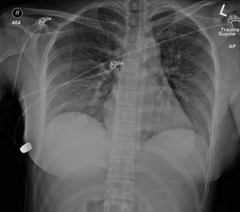

圖一是一位加拿大接受過從乳暈植入450 cc 平滑面圓盤狀矽膠義乳的女性,受到意外槍傷,子彈是0.4英吋(10 釐米)口徑的警用子彈。受傷的位置可見子彈是從左邊乳房12點鐘方向進入

圖二的正面X光可以發現在病人的右胸壁外側有一個白色的子彈。